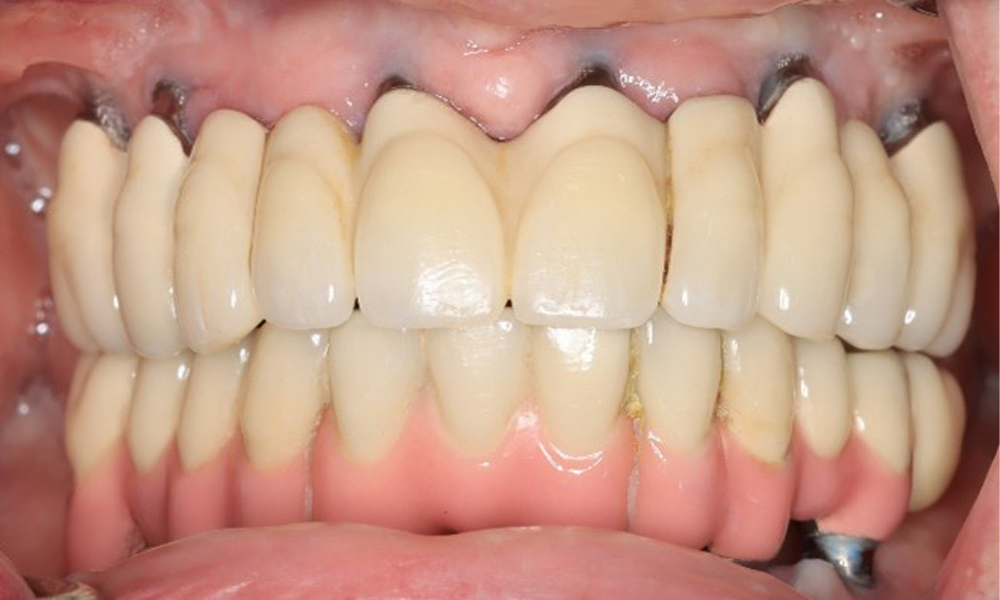

A 74-year-old patient presents for a consultation. The anamnesis shows that the patient has well-controlled hypertension and is taking Lixiana. Additionally, the patient had a kidney carcinoma in 2020. The patient’s lifestyle is unremarkable. She has no natural teeth left and has six implants in both the upper and lower jaws, which are fitted with crowns or bridges. Current findings show no peri-implant mucositis or peri-implantitis; however, there are occasional minor bleeding at the implant sites.

Front view of dentition (upper and lower jaw)

Figure 3: Frontal view